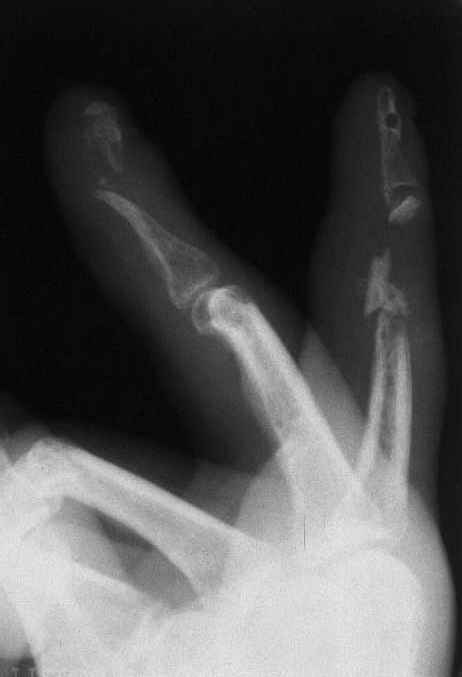

33 yo male motocross rider crashed after a jump sustaining isolated bilateral femur fxs, R side with a basicervical femoral neck and ipsilateral mid-distal 1/3 shaft, L side with a subtroch/prox 1/3 femur fx. Pt was HD stable, no LOC, GCS - 15, No other injuries, spines cleared.

The most critical injury is the proximal fracture on the right.

Sequence ­ Right neck, right shaft, then left shaft.

Implants ­ plenty of opinions exist for the right side...some would use neck screws anteriorly after reduction, then with a slender reamed locked nail

pushed in behind the neck screws for the shaft... some will advocate a recon nail for both...some will use a sliding screw for the neck then a retrograde shaft nail...some would use the sliding neck screw and a shaft plate also...lots of options.

I prefer excellent neck reduction either closed or open, screws high and low anteriorly for it, then a frail locked nail slipped in behind the neck screws for the shaft.

basicervical neck is normally treated with hip screw or cephalomedullary nail.

after perfect reduction (either closed or open) i would attempt 1 implant to treat both (i.e. TFN or Intertan). can do anything though like Dr. Routt mentioned. intertan is nice because of the rotational stability it imparts in the neck

Chip Routt listed all main options. The right proximal fracture looks closer to trochanteric. Most elegant solution would be to fix all with a single implant with minimal incisions. Long Gamma nail or any other reconstruction or proximal type nails are suitable. Technically less demanding wiuld be temporary neck pinning as is, retrograde nailing of the shaft, then final reduction and fixation of the trochanteric fracture as isolated, by DHS with 2 holes plate. Good luck.